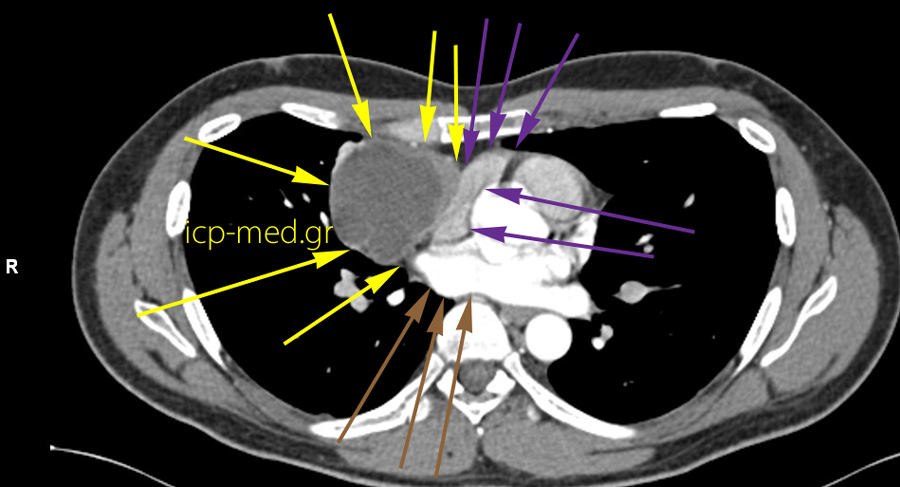

Mediastinal Seminoma, primary

5.CT: Seminoma abuts the Rigt Atrium (cavity of heart) & a Pulmonary Vein